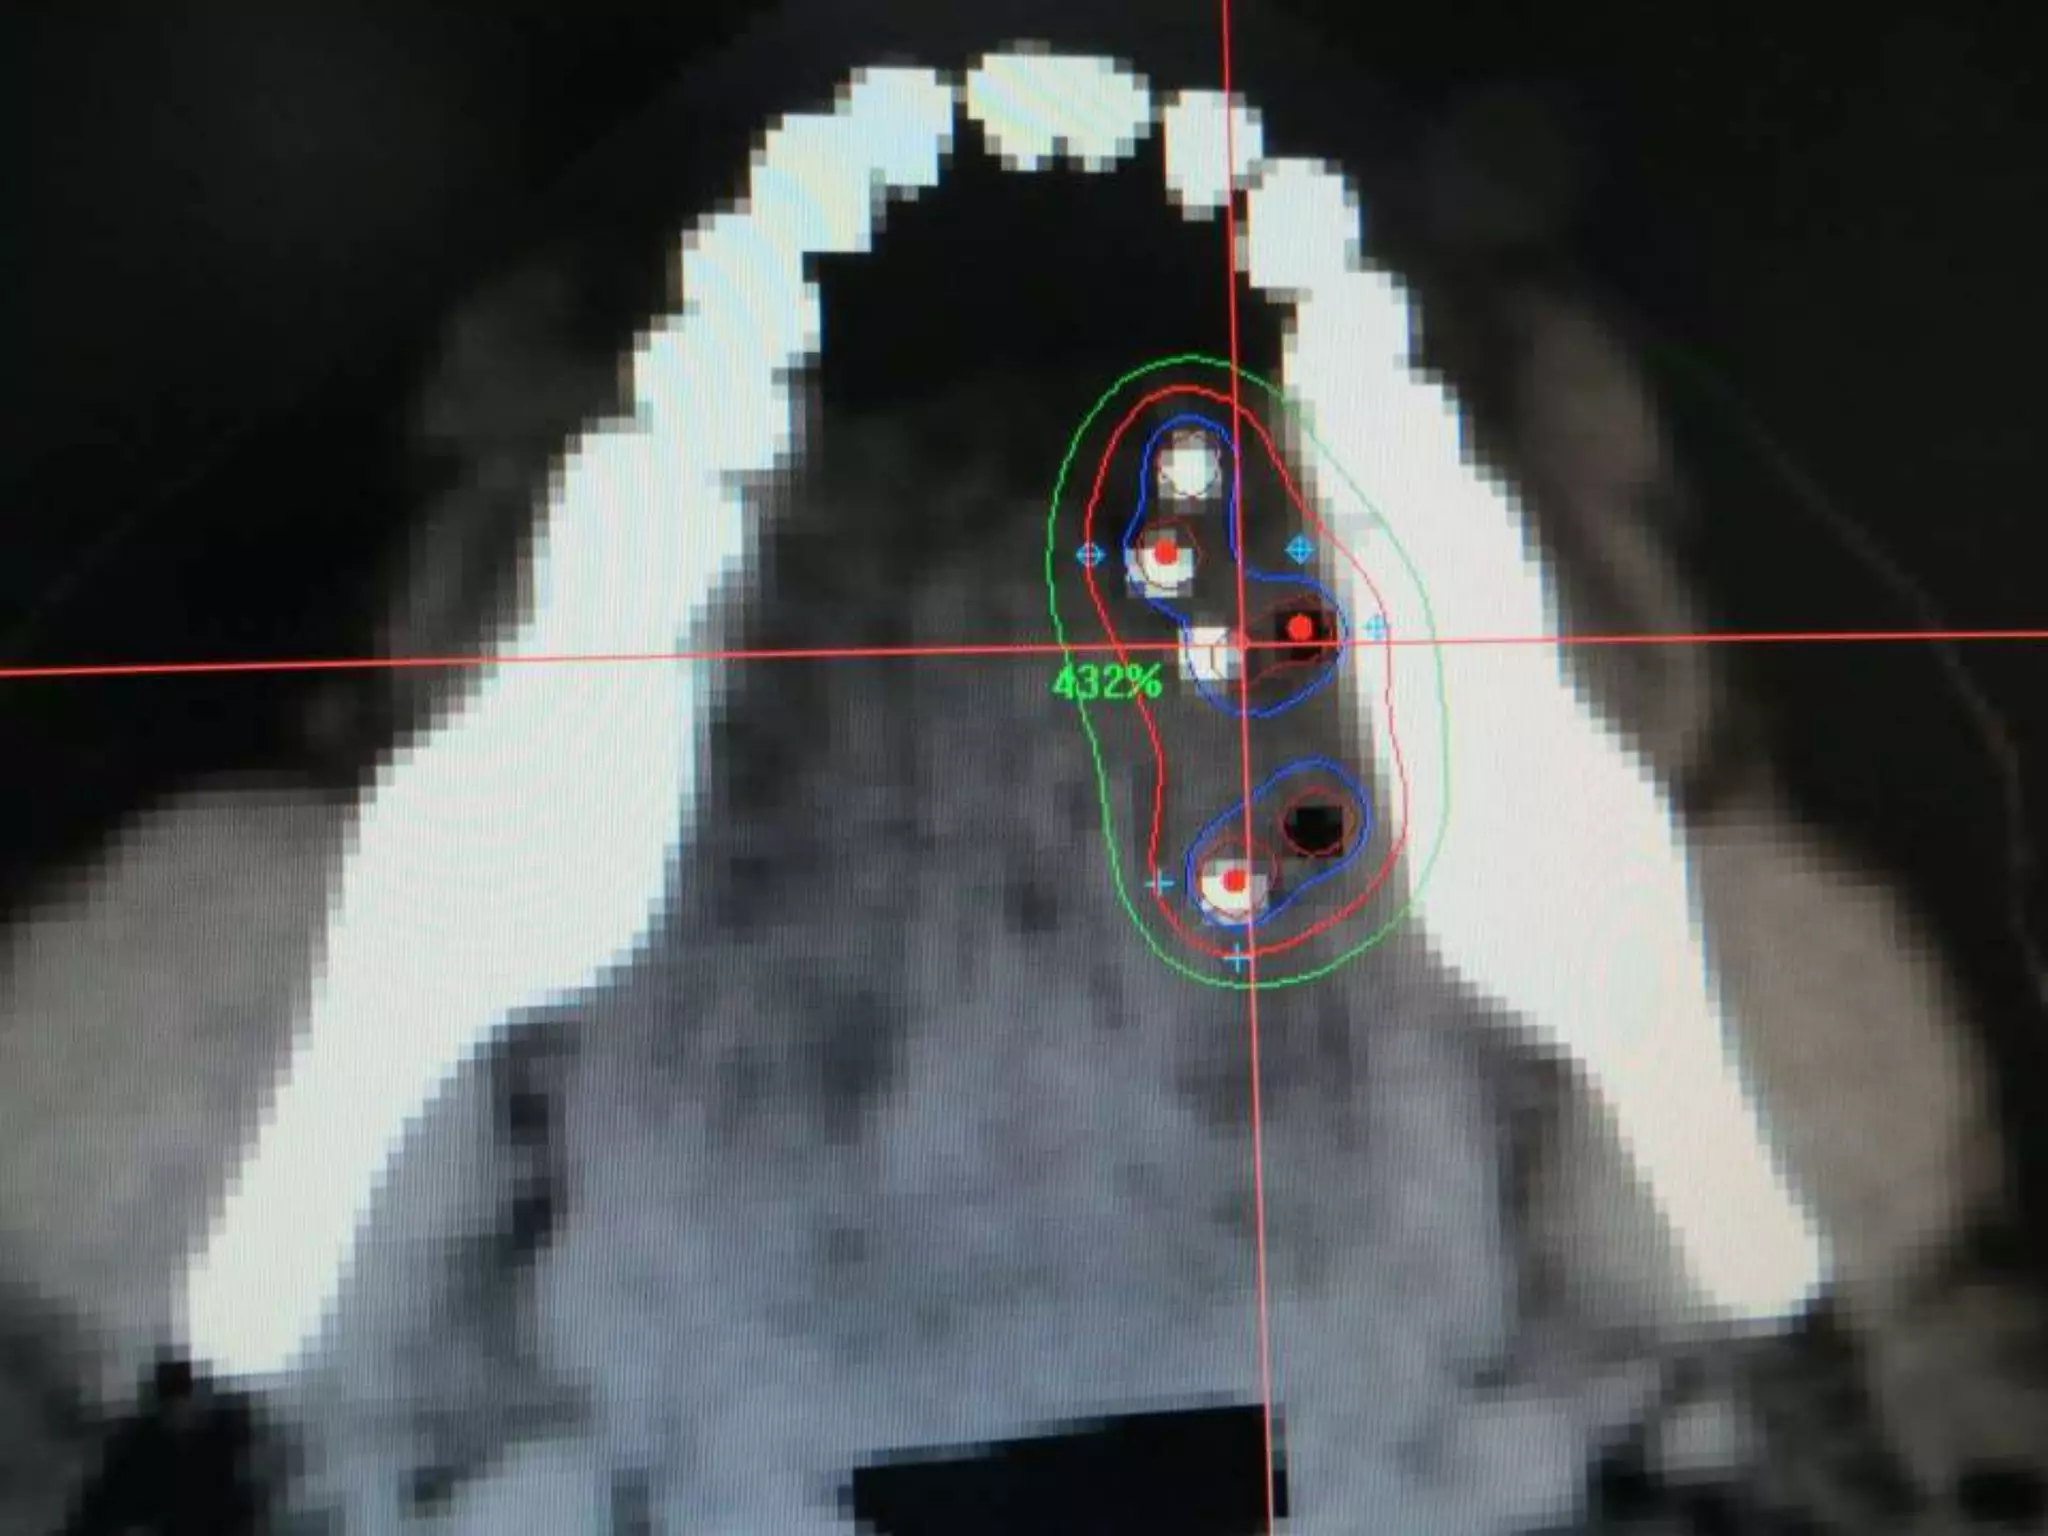

Planning-TRUS guided volume study—computer preplan

Brachytherapy procedure-TRUS guided trans perineal needle-..

peripheral loading..

seeds placed along the tract from base to apex.

Post implant evaluation-by CT scan